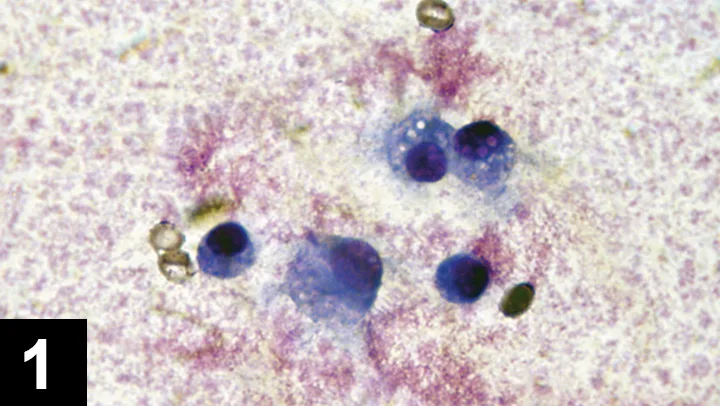

FIGURE 2 Cytology of a septic joint showing predominance of neutrophils.

Inflammatory arthropathy may be caused by infection or immune-mediated disease. Most infections are caused by bacteria; cell counts in these cases generally exceed 15,000 cells/µL (see Acquiring Cell Counts) and are predominantly neutrophilic. Gram staining and microscopic evaluation can be used to identify bacteria, but bacteria are only seen in 25% of septic arthritis cases. When such a cytologic profile has been identified, a sample should be submitted for aerobic and anaerobic bacterial culture (see If Suppurative Inflammation Is Seen). Even when bacterial infection is present, false-negative culture findings are common. Results are false-negative in about 30% to 50% of dogs with septic arthritis.1 Therefore, if septic arthritis is suspected, the clinician should institute an empirical antibiotic trial. Synovial tissue samples can also be collected for bacterial culture to improve sensitivity. Cephalexin, amoxicillin–clavulanate, or clindamycin are first-line antibiotics against Staphylococcus and Streptococcus spp, common causes of joint infection in small animals. If only one joint has suppurative inflammation, bacterial infection is probable.